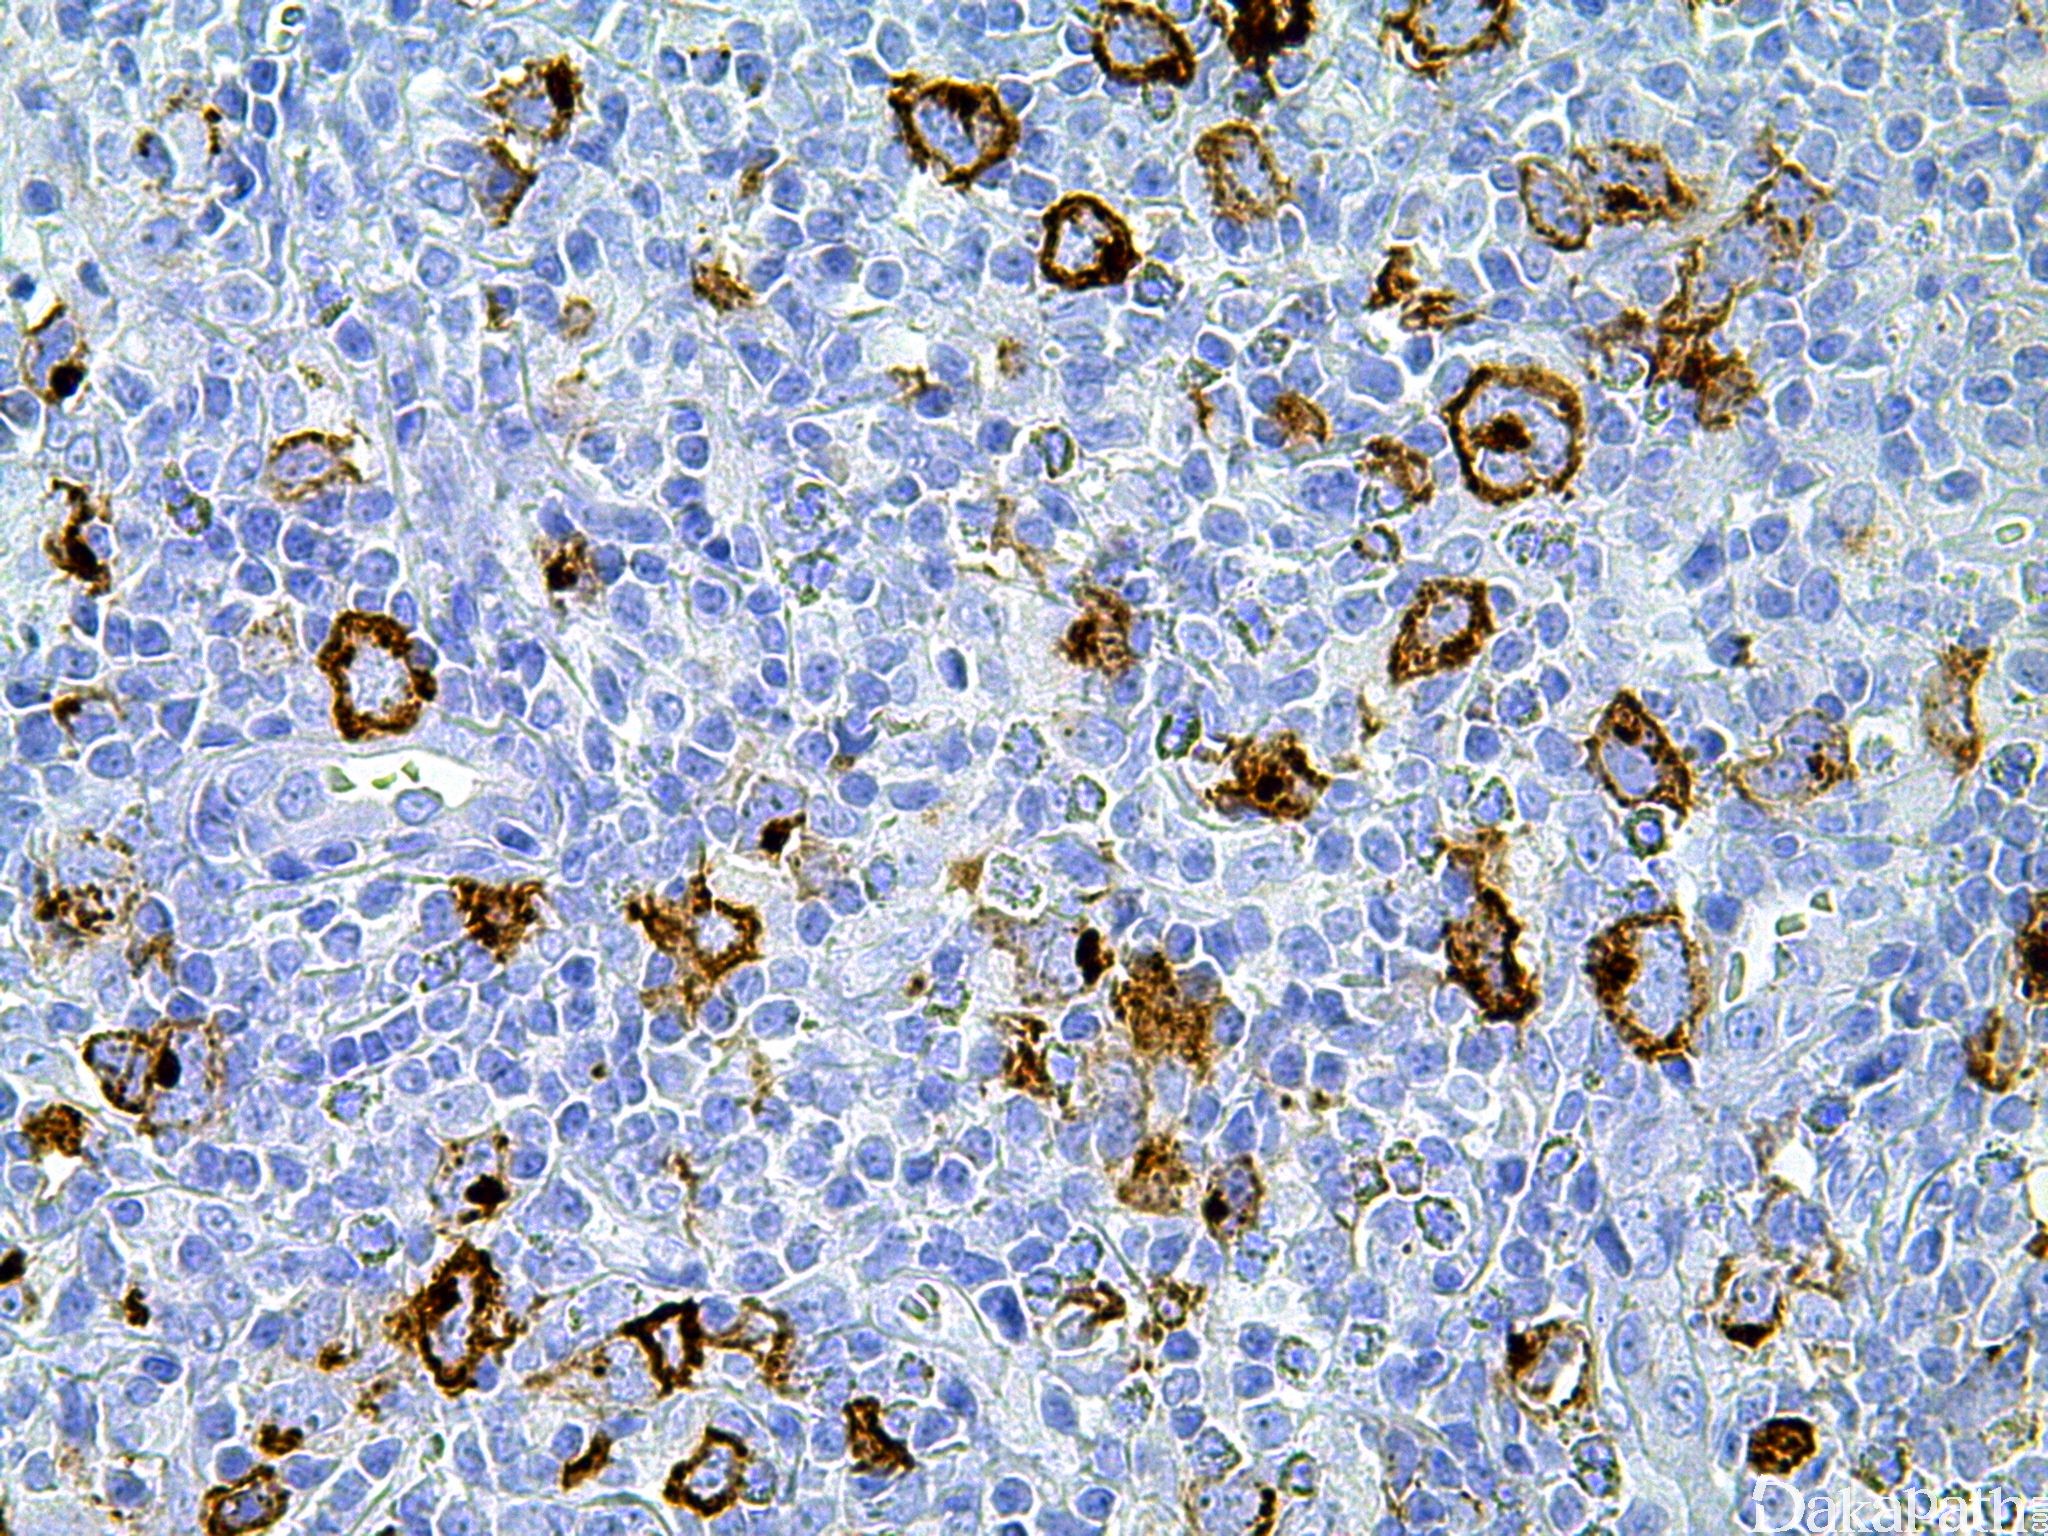

CD15

别名: LeuM1, Lewis X, 3-fucosyl-N-acetyl-lactosamine

是一种碳水化合物,标记何杰金 R-S 细胞,髓细胞白血病/肉瘤(是相对成熟髓细胞的标记物; CD117 标记相对幼稚的髓细胞,而 MPO 是相对广谱的髓细胞标记物)。腺癌阳性,可用于与间皮瘤( -)鉴别,但效果不如 BerEP4 等其它腺癌标志物。

信号定位: 胞膜、胞质

通常阳性(<95%,≥75%的病例阳性): 经典型霍奇金淋巴瘤、膀胱浸润性尿路上皮癌、膀胱腺癌,非特指型、胆管癌、淋巴细胞消减型经典型霍奇金淋巴瘤、混合细胞型经典型霍奇金淋巴瘤、结节硬化型经典型霍奇金淋巴瘤、髓系白血病、肾源性腺瘤、大汗腺混合瘤、大汗腺囊腺瘤、胰腺导管腺癌